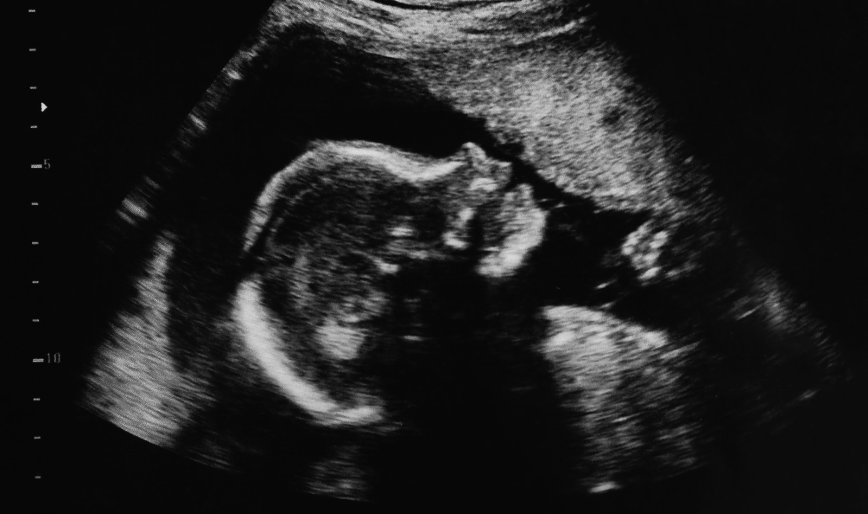

At R.K. Multispeciality Hospitals, our Maternity Care department is dedicated to providing safe, compassionate, and personalized care for expectant mothers. We guide you through every stage of pregnancy, ensuring a healthy and positive experience for both mother and baby.

Our approach focuses on comprehensive prenatal care, including regular check-ups, nutritional counseling, and birth planning. We provide a supportive environment, with experienced obstetricians and nurses who prioritize your comfort and safety.